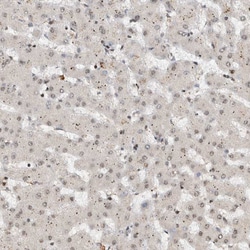

Invitrogen™ ZNF521 Polyclonal Antibody

Brand: Invitrogen™ PA554898

| Immunohistochemistry (Paraffin) | |

| Recombinant protein corresponding to Human ZNF521. Recombinant protein control fragment (Product #RP-93654). | |